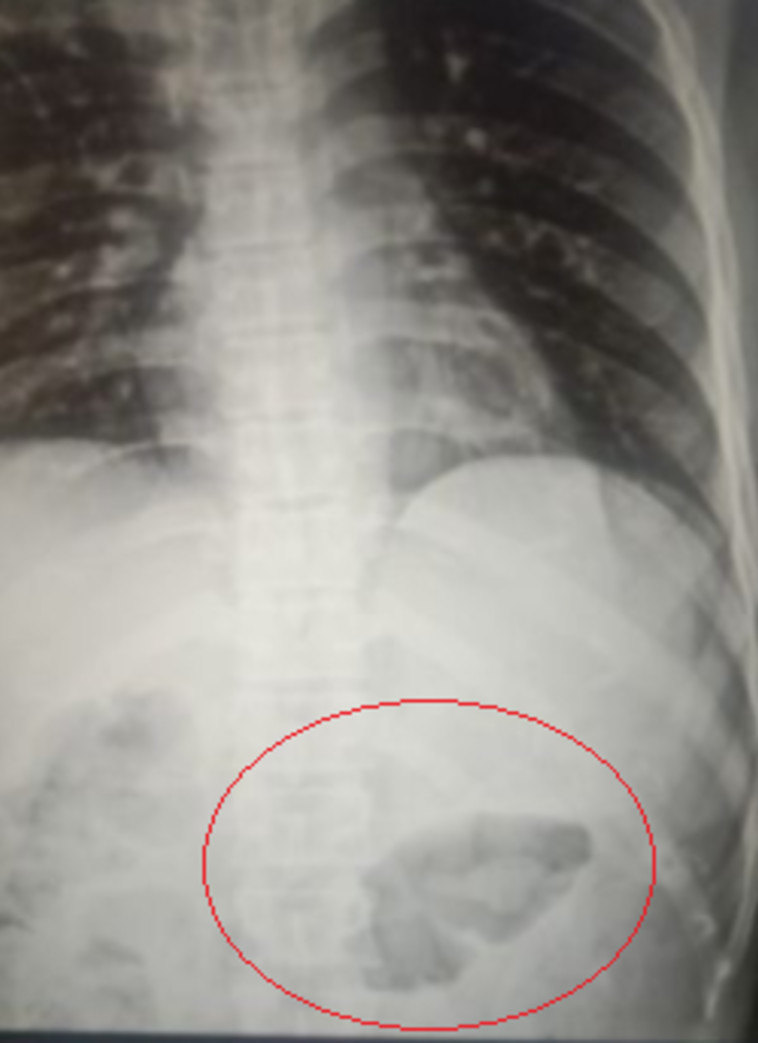

הקליע בצילום הרנטגן

הקליע בצילום הרנטגן | צילום: Dr Vardharam Dewasi

צילום הרנטגן של צ'אנד חשף כי הקליע היה מתחת לעורו, אך במזל גדול הוא לא פגע באף אחד מהאיברים החיוניים. רק ביום שישי בבוקר, אחרי יותר מ-24 שעות עם הקליע בגופו, העובד נכנס לניתוח כדי להסיר את האיום. האורתופד ורדהארם דיוואסי, שהיה אחראי על הניתוח, שטף היטב את גופו של צ'אנד ומנע זיהום רציני שהיה עשוי להתפשט בעקבות הפציעה. כמו כן, המשטרה המקומית בוחנת את הסיטואציה ומתייחסת למקרה כאל חקירת ניסיון רצח.